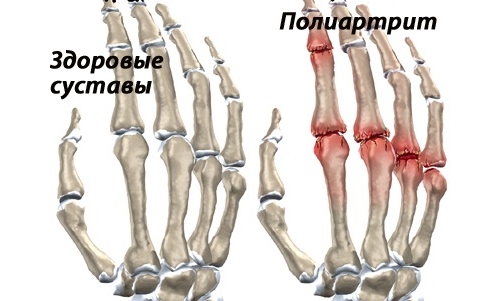

К главным симптомам ревматоидного полиартрита относятся суставные боли и деформации мелких суставов. Часто поражаются мелкие суставы кистей рук и пальцев. Для данной патологии характерна симметричность поражения суставов. В зависимости от количества вовлеченных суставов, врачи определяют стадию и вариант течения заболевания.

Деформация суставов пальцев у больного ревматоидным полиартритом

Картина поражения суставов

Поражение кисти - одна из главных визитных карточек полиартрита